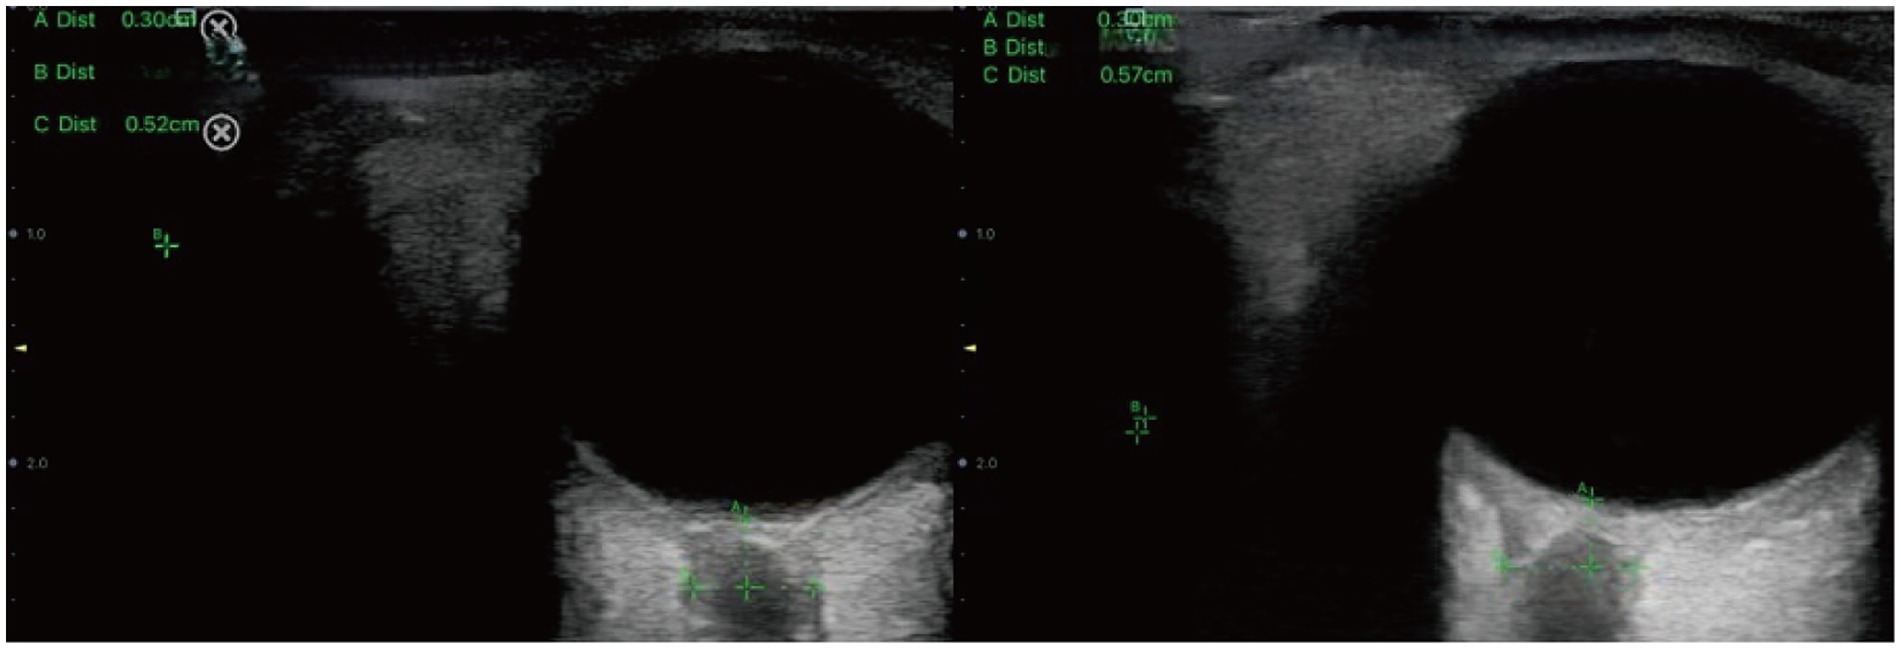

During the procedure, patients were positioned supine with their head elevated at 20° to 30°, maintaining a neutral head position and keeping their eyelids naturally closed. A sufficient amount of ultrasound gel was applied to the probe, which was gently placed on the closed upper eyelid. The clearest cross-sectional view of the optic nerve without artifacts was selected for measurement. ONSD was measured 3 mm behind the globe, perpendicular to the optic nerve axis (Figure 1). Three measurements were obtained in both the transverse and sagittal planes for each eye, resulting in six values per eye. The average of these six values for each eye was used for data analysis.

Figure 1. Sonographic measurement of the ONSD 3 mm behind the eyeball. The left ONSD was 0.52 cm in a patient from Group 1, and the right ONSD was 0.57 cm in a patient from Group 2.